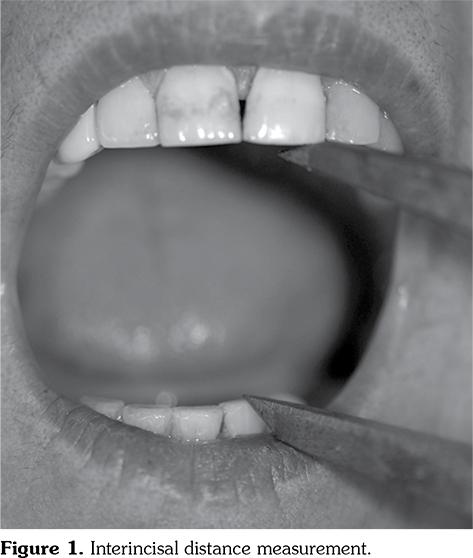

Patients were referred to the Faculty of Dentistry for the interincisal distance (ID) measurement. An experienced dentist performed the dental examination of this study. The maximal mouth opening capacity (MOC) was measured using the ID between the maxillary and mandibular central incisors in the midline as described by Wood and Branco.[19] Before measuring MOC, the subjects were asked to rest in the visiting area for at least 10 minutes. MOC was measured for each subject in the Frankfort horizontal plane (a line from the tragus of the ear through the palpable bony infraorbital rim area), which was oriented parallel to the floor, according to the natural head position in a dental unit. The subjects were asked to open their mouths as wide as they could with no pain. The linear distance from the incisal edge of the upper central incisor to the incisal edge of the lower central incisor was recorded using a dental bow compass and measured with a millimeter ruler. Each subject was measured three times every two minutes and the highest value of these three measurements was recorded (Figure 1).[20]